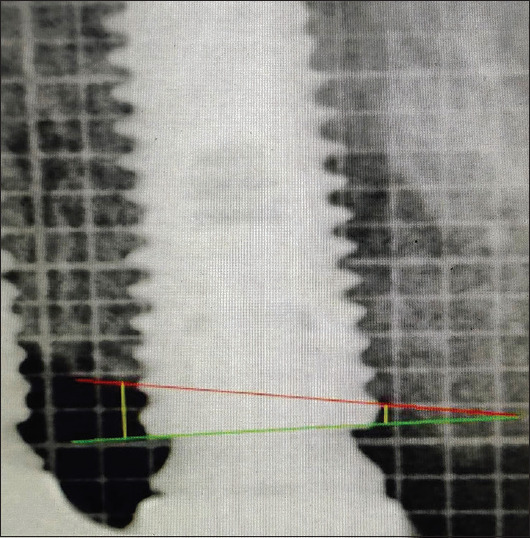

Materials and methods: A total of 15 patients were evaluated, in 2 years, for study purpose. Among 87 immediately loaded implants, 44 were IPIL and 43 were HSIL. The bone level was measured using Implant abutment junction as reference point, at 0, 6, 12, 18 and 24 months. Bone loss was calculated as difference of mean.

Results: The average bone loss for 2 years was 1.39 mm and 1.17 mm, in IPIL and HSIL group respectively with 100% implant survival rate and no statistical difference (P < 0.05).